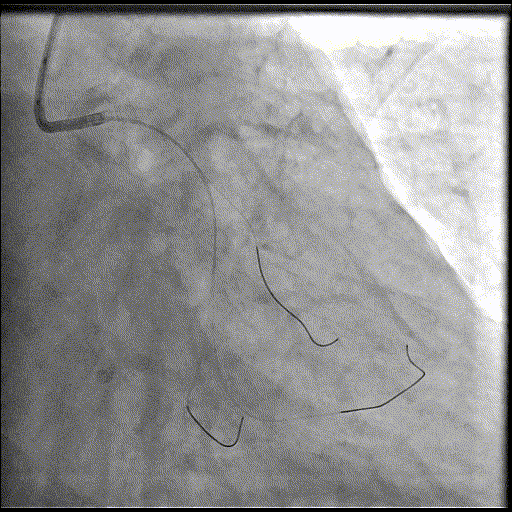

手术过程

导丝到位

当指引导管冠脉开口到位后,选择三根对应导丝分别送入LCX、OM1、OM2远端。

OM2优先处理:

球囊预扩

当导丝通过病变后其他器械无法通过病变,此时选择不同尺寸的小球囊逐级预扩张病变,复查造影狭窄减轻不明显。为了解血管真实情况,遂启用IVUS检查。

术前腔内影像学IVUS指导

IVUS提示血管可见钙化明显,为360°环形钙化。遂考虑启动IVL治疗。

冲击波球囊治疗

2.5*12mm@4atm 冠脉血管内冲击波导管反复进行4个周期治疗,复查造影提示狭窄减轻。

支架植入并后扩

于OM2-LCX远端植入一枚药物洗脱支架,经非顺应性球囊后扩张支架,复查造影提示支架贴壁良好,未见夹层、血肿。